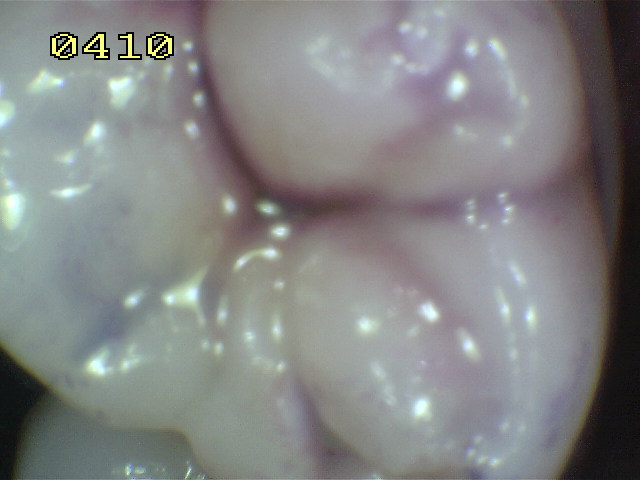

Este índice es utilizado para evaluar la higiene de las caras oclusales. Para ello se utiliza una solución reveladora de placa bacteriana (doble tono). El paciente debe realizar un buche con agua para eliminar el exceso de colorante. En el siguiente cuadro se observa los criterios utilizados:

Índice de placa oclusal

0

No hay placa.

1

Placa de color rosa en surco.

2

Placa de color rosa en surco con islotes azules.

3

Placa de color azul en surco.